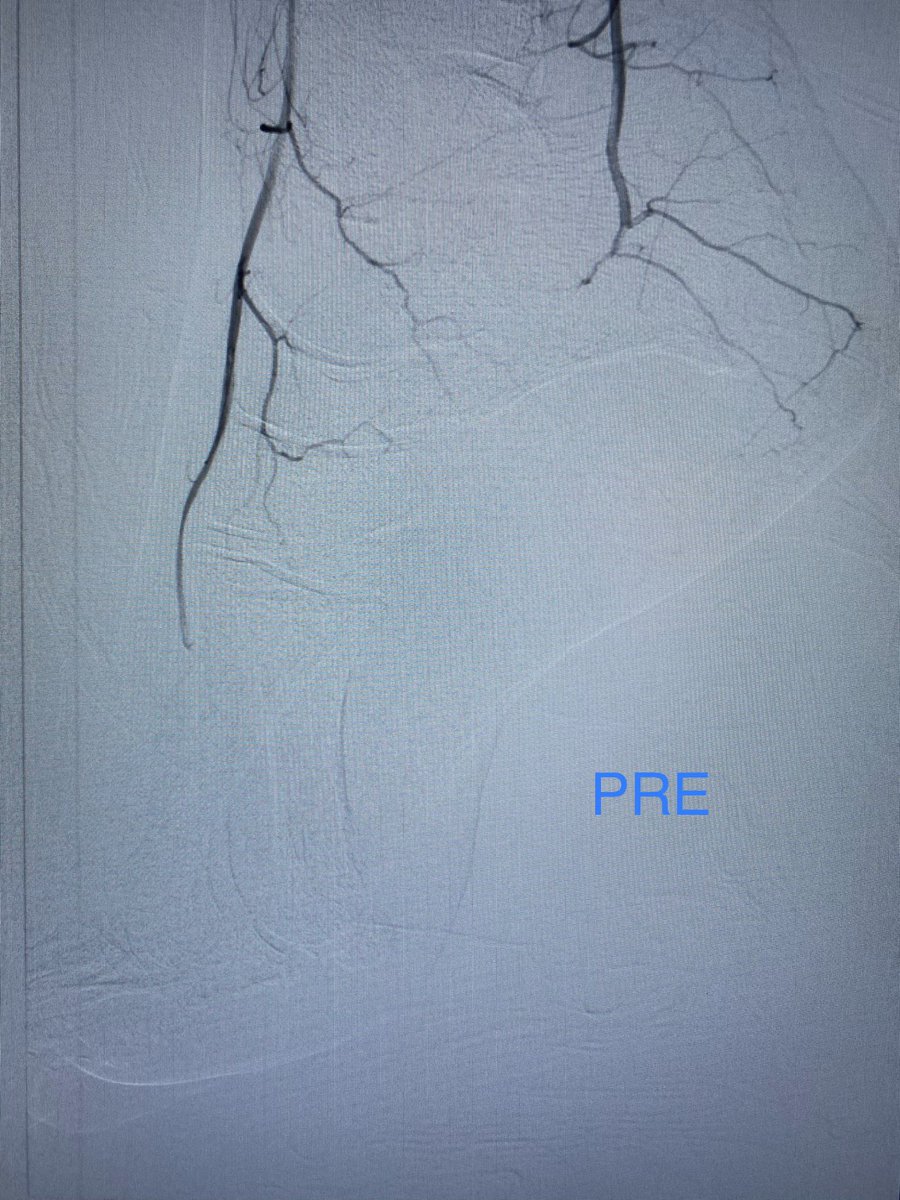

Our IR Section Chief @arzybule demonstrating his skills utilizing #nBCA to embolize a large shoulder AVM with our amazing #ESIR residents @Rubin129 #DannyReyes! Everybody loves a GlueEmbo case!!!